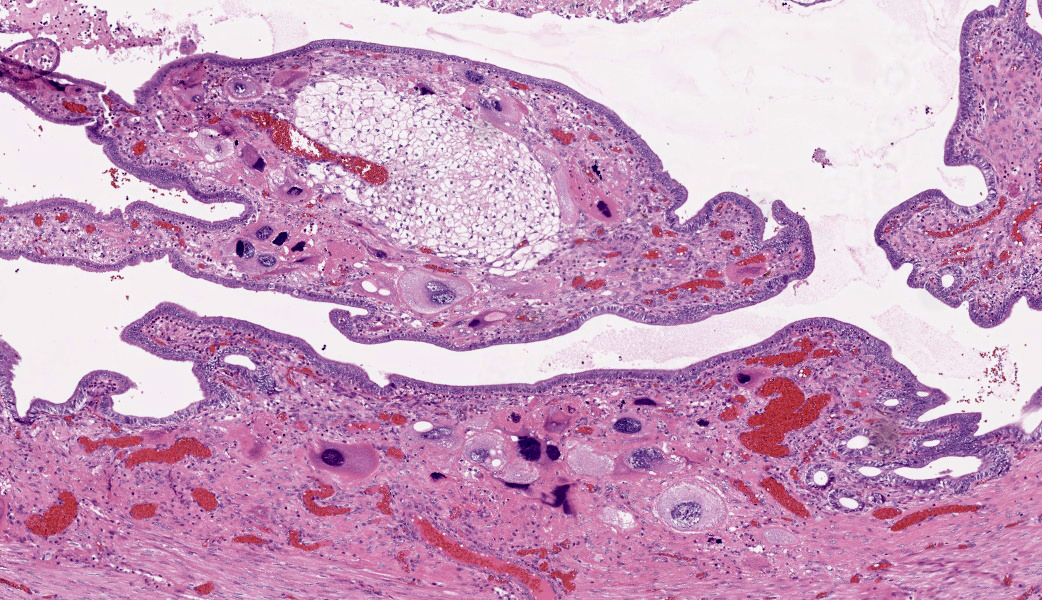

The endometrium on the mesometrial side of the uterus proliferated with the formation of large nodules and numerous polyps. The surface of the nodules and polyps was covered by endometrial epithelium, however, approximately 50% of the epithelium were eroded. The polyps and nodule contained numerous blood vessels with normal endothelium, along with cells that resembled large-vacuolated decidual cells, arranged in sheets. The decidual cells had distinct cell boundaries, a round shape, abundant transparent cytoplasm, and nuclei ranging from oval to irregular shapes. Mitotic figures were also occasionally observed. Just beneath the endometrial epithelium, the decidual cells exhibited a spindle-shaped morphology. (Fig.1 and 2)On the antimesometrial side of the uterine, endometrial hyperplasia was mild, decidual cells in the endometrial stroma were sparse, and proliferation of huge giant cells resembling trophoblast was prominent. The huge giant cells displayed a variety of morphologies, including round, spindle, to pleomorphic, with notably large, highly atypical nuclei and abundant cytoplasm. Multinucleated giant cells were also observed.The immunohistochemical analysis demonstrated that normal endometrial epithelium is positive for progesterone receptor (PgR), keratin AE1/AE3, and CAM5.2, and negative for CD10, SMA and desmin. Normal endometrial stromal cell is positive for PgR and CD10, and negative for keratin AE1/AE3, CAM5.2, SMA and desmin. Decidual cell is positive for PgR and CD10, and negative for keratin AE1/AE3, CAM5.2, SMA and desmin. The huge giant cells exhibited positive for keratin AE1/AE3, CAM5.2 and CD10, and negative staining for PgR, SMA and desmin.

Rabbits have a hemodichorial and bidiscoid type of placenta. Histologically, the placenta of rabbits is composed of the labyrinth zone, the junctional zone, the decidua zone, and the mesometrium.3,6,7 In the labyrinth zone, there are two layers of trophoblasts, an outer and inner layer separating the maternal blood spaces from the fetal blood vessels. The outer trophectoderm is comprised of the syncytiotrophoblasts. The inner trophectoderm is one layer of cytotrophoblasts overlying fetal blood vessels. The junctional zone is composed of glycogen cells with eosinophilic cytoplasm containing PAS-positive substances and giant cells having often 2-3 number of nuclei. The decidua originates from stromal cells of the mesometrial endometrium. Before 11 days of pregnancy, it consists of proliferating spindle cells, subsequently, vacuolated cells known as decidual cells begin to appear. The proliferation of decidual cells continues, and from 13 days of pregnancy, necrosis of decidual cells begins to be observed. In mid-gestation, the decidual zone is divided into the zone of necrosis and the zone of separation. 3,6,7 The zone of necrosis develops with dilated blood vessels as pregnancy advances. This zone is detected under the junctional zone and is composed of necrotic tissue. The zone of separation, which is composed of the cells having large foamy cytoplasm, becomes thinner without necrosis as pregnancy advances. 3,6,7During pregnancy in rabbits, a characteristic feature is the presence of giant cells on the obplacental (antimesometrial) region. These giant cells are referred to as obplacental giant cells to distinguish them from certain cell populations of the definitive (chorioallantoic) placenta and decidua. 1 Immunocytochemistry shows that the giant cells are positive for cytokeratin and vimentin, but are negative for desmin and Factor VIII-related antigen. The cells are positive for cytokeratin from their inception, but only become vimentin-positive between Days 12 and 15 of pregnancy, a change seemingly related to their detachment from epithelial tissue to take on an independent existence.

In contrast, numerous giant cells were observed on the obplacental (antimesometrial) region. These giant cells are similar to obplacental giant cells formed in the pregnant uterus of rabbits with regard to both cell morphology and location. 1 The origin of these cells remains unclear. The absence of obvious trophoblasts and the formation of giant cells in the endometrial stroma beneath the normal endometrial epithelium suggest a uterine origin. However, immunostaining revealed positivity for CK and CAM5.2 (epithelial marker) and CD10 (positive for endometrial stromal cell), and negative for PgR (positive for both endometrial epithelial and stromal cell), which did not correspond with the staining patterns of endometrial epithelial or stromal cells. Consequently, it was not possible to ascertain their origin with any degree of certainty.